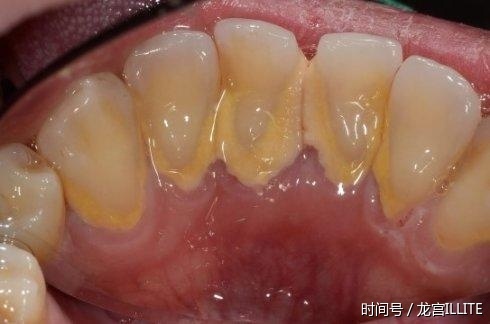

| 什么是牙结石? 牙结石的存在是百害无一利,他会引起牙龈出血,口臭和一些牙周疾病等不良症状,最大的危害在于牙结石会不断的在增加,将牙龈和牙齿隔绝开来,形成牙龈萎缩,长时间不治疗的话,牙齿就变得松动和坠落。

牙结石就是口腔内的牙垢,食物残渣终年堆积、钙化在牙齿表面构成坚固的堆积物,紧紧附着在牙齿、牙周表面,它是由75%的磷酸钙,15%~25%的水、有机物、磷酸锰、矿酸钙及微量的钾、钠、铁所构成。牙结石初步是乳白色的软垢,逐渐钙化而变硬,变硬后的牙结石很难通过日常的刷牙来根除掉,如果不去专业的牙科安排洗牙,就得不到完全的洁治。 据调查显示,约98%的人就算早晚刷牙漱口,也仍是会长牙结石。所以牙结石的构成不只仅跟刷牙有关,口腔内唾液碱化,牙龈中的磷酸酯酶升高、身体免疫力差等等,都会诱发牙结石。 除了一天2-3次洗牙,还有什么方法能快速根除口腔内的牙结石呢? 许多人不愿意去医院洗牙,但是为了口腔健康,避免牙结石诱发牙龈炎、牙周炎等疾病,牙结石是有必要去除的。日子中去除牙结石的小窍门也有不少,龙宫口伊利石口腔专家今天也给我们介绍几个。1、橘子皮晒干橘子皮成效类似于柠檬,但运用方法略有不同,桔子皮晒干,磨成粉,和牙膏混在一起刷牙,牙齿不只能敏捷变白还能去除牙垢。2、墨鱼骨根除法乌贼骨50克研成细末,掺在牙膏内,每日2次可除黄色、黑色牙垢。 3、核桃壳 这种方法不只在国内民间被广泛运用,在一些日韩国家也很盛行呢,因为它比市面上许多去牙结石的产品更天然,无副效果。核桃壳归于软质植物抛光材料,具有抗菌生物活性,所以只需加水熬煮就可以去除牙垢,或是治疗牙龈出血。 详细运用方法 在锅里放入30-40克的核桃壳,加250克的水,将核桃壳熬水煮20分钟 (水要盖过核桃壳)。 等核桃糊冷却后,将牙刷浸置其间10分钟,然后像一般刷牙的方法一样清洁牙齿。 刷完牙往后记住再多漱几回口,将牙齿里的核桃残渣去除,避免伤到牙龈。 这个核桃糊一天可以运用三次,最多可以用两天,如果逾越两天的话,主张从头煮新鲜的。 4、新鲜柠檬汁刷牙,不只去牙结石还能皎白牙齿。 柠檬富含维生素C和维生素P,能增强血管弹性和耐性,强固齿根,并且柠檬的洗净力强,有皎白牙齿成效。柠檬法虽然对牙垢和美白牙齿有必定效果,但是不能长时间运用,因为柠檬有必定的酸性,运用要适量,不然会伤害到牙齿。 柠檬去皮榨成汁,每晚刷洗完牙齿之后,用棉签蘸少量的柠檬汁擦拭每颗牙齿,一次蘸4、5滴,来回蘸个6次就悉数擦拭到了,必定要均匀涂擦,不然第二天牙齿的颜色会不均匀。 把柠檬汁和牙膏一起运用,用牙膏蘸少量的柠檬汁一起刷牙齿,坚持横竖替换刷牙的方法,刷牙时间不能低于2分钟,这关于发黄、有牙垢的牙齿效果很不错。 刷牙前含一口柠檬汁,含2,3分钟后刷牙,坚持2周就会有效果。 5、食醋刷牙法——根除牙结石、除口臭 其一,把食醋含在嘴里,鼓漱2~3分钟后吐掉,然后再用温水刷牙。大约2月一次,用于救急仍是不错的,不能常用,不然会使牙齿酸麻 其二,刷牙时,在牙膏上滴两滴食醋,坚持此法刷牙2周左右会有成效。 7、酵母粉刷牙 早晚刷牙时,将牙膏蘸上少量的酵母粉,这样刷牙还有美白牙齿的成效,传闻许多模特运用此方法,如果没有酵母粉,也可用小苏打或许白矾末代替。 8、花生冲突法 花生中油酸含量高达50%以上,油酸对人体心血管有利,对人体的高血脂、有害胆固醇有下降效果,用在口腔内,对保护牙龈和去除牙结石有很好的效果。直接把花生放入口中嚼碎,不要吃,把它当牙膏用来刷牙,颗粒状的花生屑可以将牙垢磨除。 |